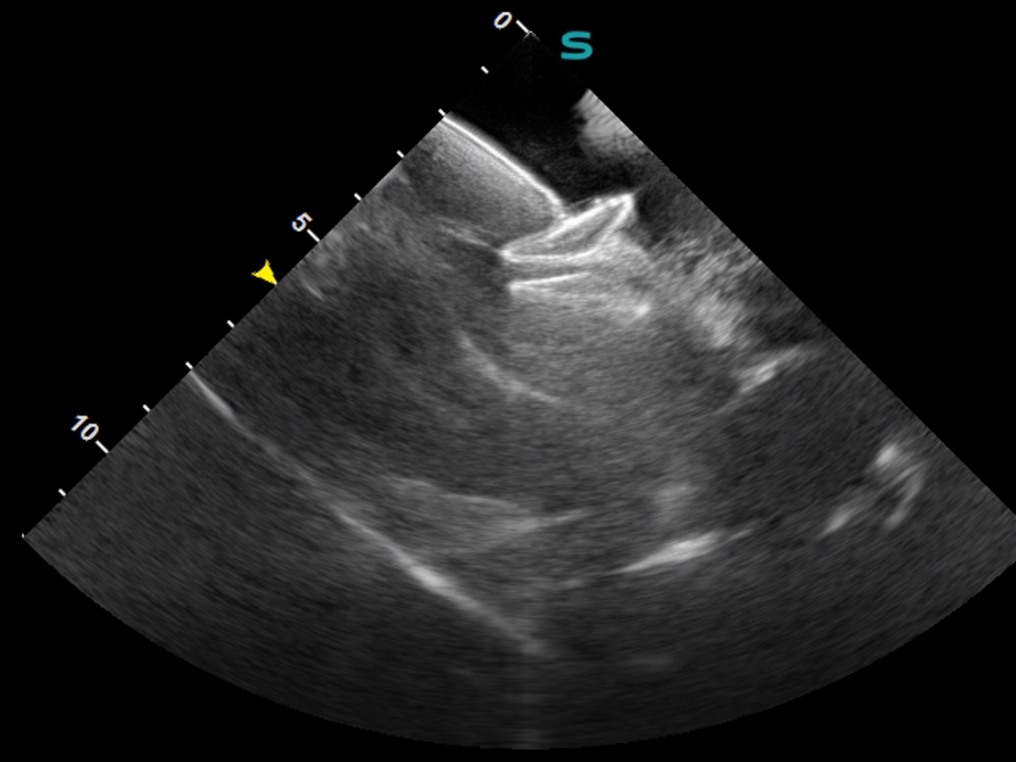

ICE导管经股静脉入路输送至患者的右心房,通过导管调弯,可以清晰观察到右心房、右心室、三尖瓣、房间隔、左心房、左心耳、左心室、二尖瓣等心脏结构,并通过超声心动图完成了血流的评估和卵圆孔未闭的评估。在ICE的指导下,封堵器一气呵成地完成释放。术后实时的超声心动图显示封堵器位置固定完美,封堵效果理想,手术取得圆满成功。ICE系统的超声影像质量和导管操控性能均表现优异,获得了临床专家的一致好评。

影像图片

ICE指导房间隔穿刺

ICE评估PFO封堵效果